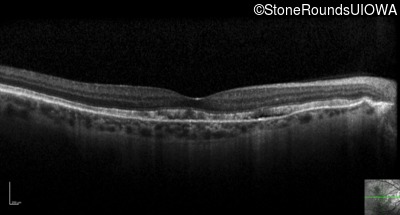

Optical Coherence Tomography - Left - 20/30 -2 sc

Exemplar / OCT Stack